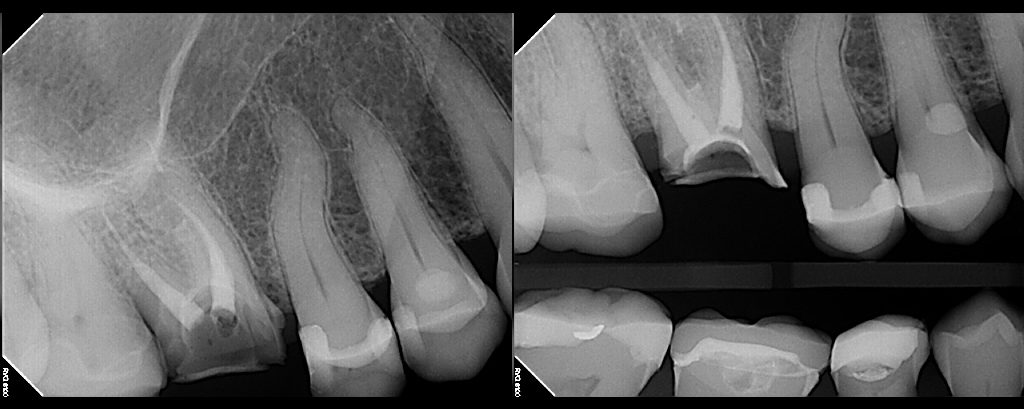

This 35 year-old male presented as an emergency with acute pain in the lower left quadrant.  Obvious deep caries present in both #19 and #18.  Tooth #19 was acutely painful to the touch.  His general dentist told him that both teeth were non-restorable and needed to be extracted.  He did not want to lose both […]